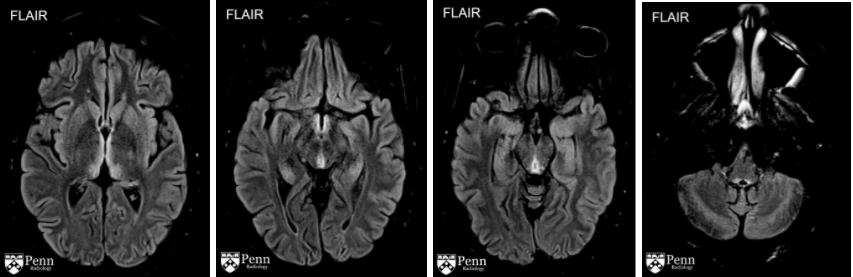

5.2. MRI não

MRI là phương thức hình ảnh thường được lựa chọn.

Trên hình MRI cho thấy những thay đổi phù nề hoặc viêm, đặc trưng bởi tăng tín hiệu trên hình T2 và FLAIR ở thể vú, chất xám quanh cống não và quanh não thất, củ não sinh tư và đồi thị. Teo các cấu trúc não này cũng có thể thấy được. Có thể thấy tổn thương ngấm thuốc tương phản và hạn chế khuếch tán, nhưng không phải là điều kiện cần để chẩn đoán. Sự ngấm thuốc tương phản thường thấy ở thể vú.